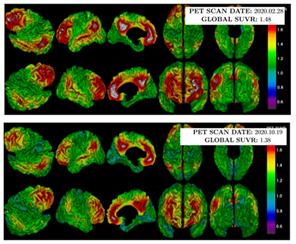

환자들은 개방술을 받은 6개월 동안 약을 복용했고 연구 중에 아밀로이드 침착을 확인하는 PET 검사를 시술 전후로 2번 진행했다. 연구팀은 PET 검사 수치를 보정해 ‘표준화 섭취계수율’로 아밀로이드 감소 정도를 파악했다. 보호자를 대상으로는 행동과 심리를 기반으로 치매 중증 정도를 파악하는 CGA-NPI(Caregiver-Administered Neuropsychiatric Inventory)을 실시했다.

뇌혈관장벽 개방술 전(위), 후(아래) 아밀로이드 PET 검사 결과, 후 사진에서 아밀로이드 양과 범위(회색+빨간색)가 감소한 것을 확인할 수 있다.

연구 결과, 마지막 검사의 표준화 섭취계수율은 환자 평균 0.986으로 첫 검사 결과인 1.002보다 0.016 하락해 아밀로이드가 감소한 것으로 밝혀졌다. CGA-NPI 점수는 8점에서 2점으로 떨어지며 보호자가 느끼는 환자 문제 행동도 호전됐다.